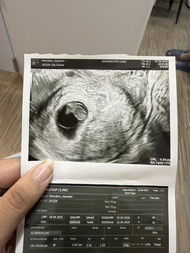

กี่ weeks ถึงจะตรวจเจอการเต้นของหัวใจลูกน้อยคะ

ตอนนี้น้อง 6 weeks 2 days

ซาวด์ตอน6+6ค่ะ แต่เครื่องบอก6+4 เห็นหัวใจแล้วค่ะ คุณหมอชี้ให้ดู คุณหมอบอกที่กระพริบๆอยู่อันนั้นคือหัวใจ

นับตามประจำเดือน 7 วีค แต่ในใบซาวน์ 6วีค 4วันค่ะ เจอตัวน้อยพร้อมหัวใจเต้น ซาวน์ผ่านหน้าท้องค่ะ